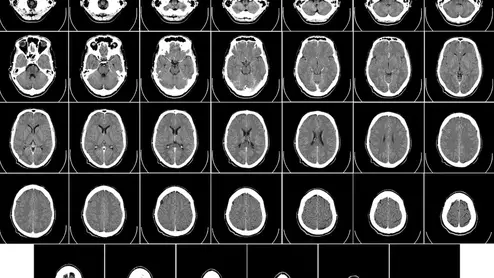

Head CT

The FDA has cleared an investor-backed teleradiology provider to market two AI algorithms the company developed to flag certain stroke-associated findings in images from head CT scans.

The approval, made as part of a special FDA pilot program, took just 50 days.